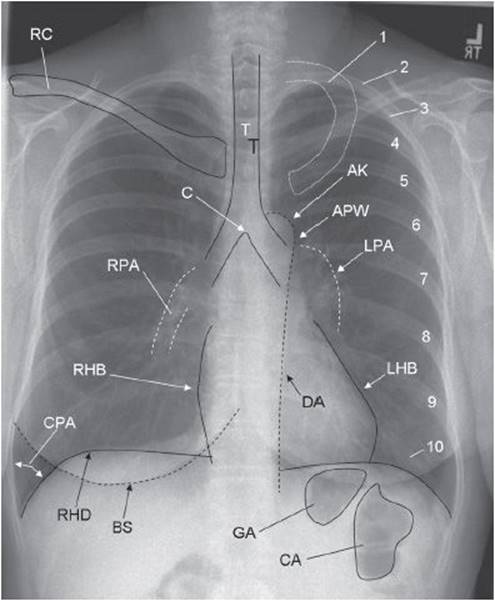

E—Everything else. Now it is time to look at the lungs. Start with the trachea. Is it midline? Are any of the lobes opacified? Are there any tumors? Make sure you scan throughout the right and left lungs. Classic blind spots are the lung apices and lung behind the heart. Also note the pattern of an abnormal opacity. Is the process diffuse or localized? More central or peripheral? Hazy or linear? Does the opacity obscure a normal silhouette? For example, opacities that block the left or right heart borders represent an abnormality in the lingula or right middle lobe, respectively, whereas opacities obscuring either diaphragm are in the lower lobes. See Figure 25-1.

Figure 25-1. Structures seen on a posteroanterior (PA) chest x-ray. 1, first rib; 2–10, posterior aspect of ribs 2 to 10; AK, aortic knob; APW, aortopulmonary window; BS, breast shadow (labeled only on right); C, carina; CA, colonic air; CPA, costophrenic angle; DA, descending aorta; GA, gastric air; LHB, left heart border (Note: Most of the left heart border represents the left ventricle; the superior aspect of the left heart border represents the left atrial appendage); LPA, left pulmonary artery; RC, right clavicle (left clavicle not labeled); RHB, right heart border (Note: The right heart border represents the right atrium); RHD, right hemidiaphragm (left hemidiaphragm not labeled); RPA, right pulmonary artery; T, tracheal air column.